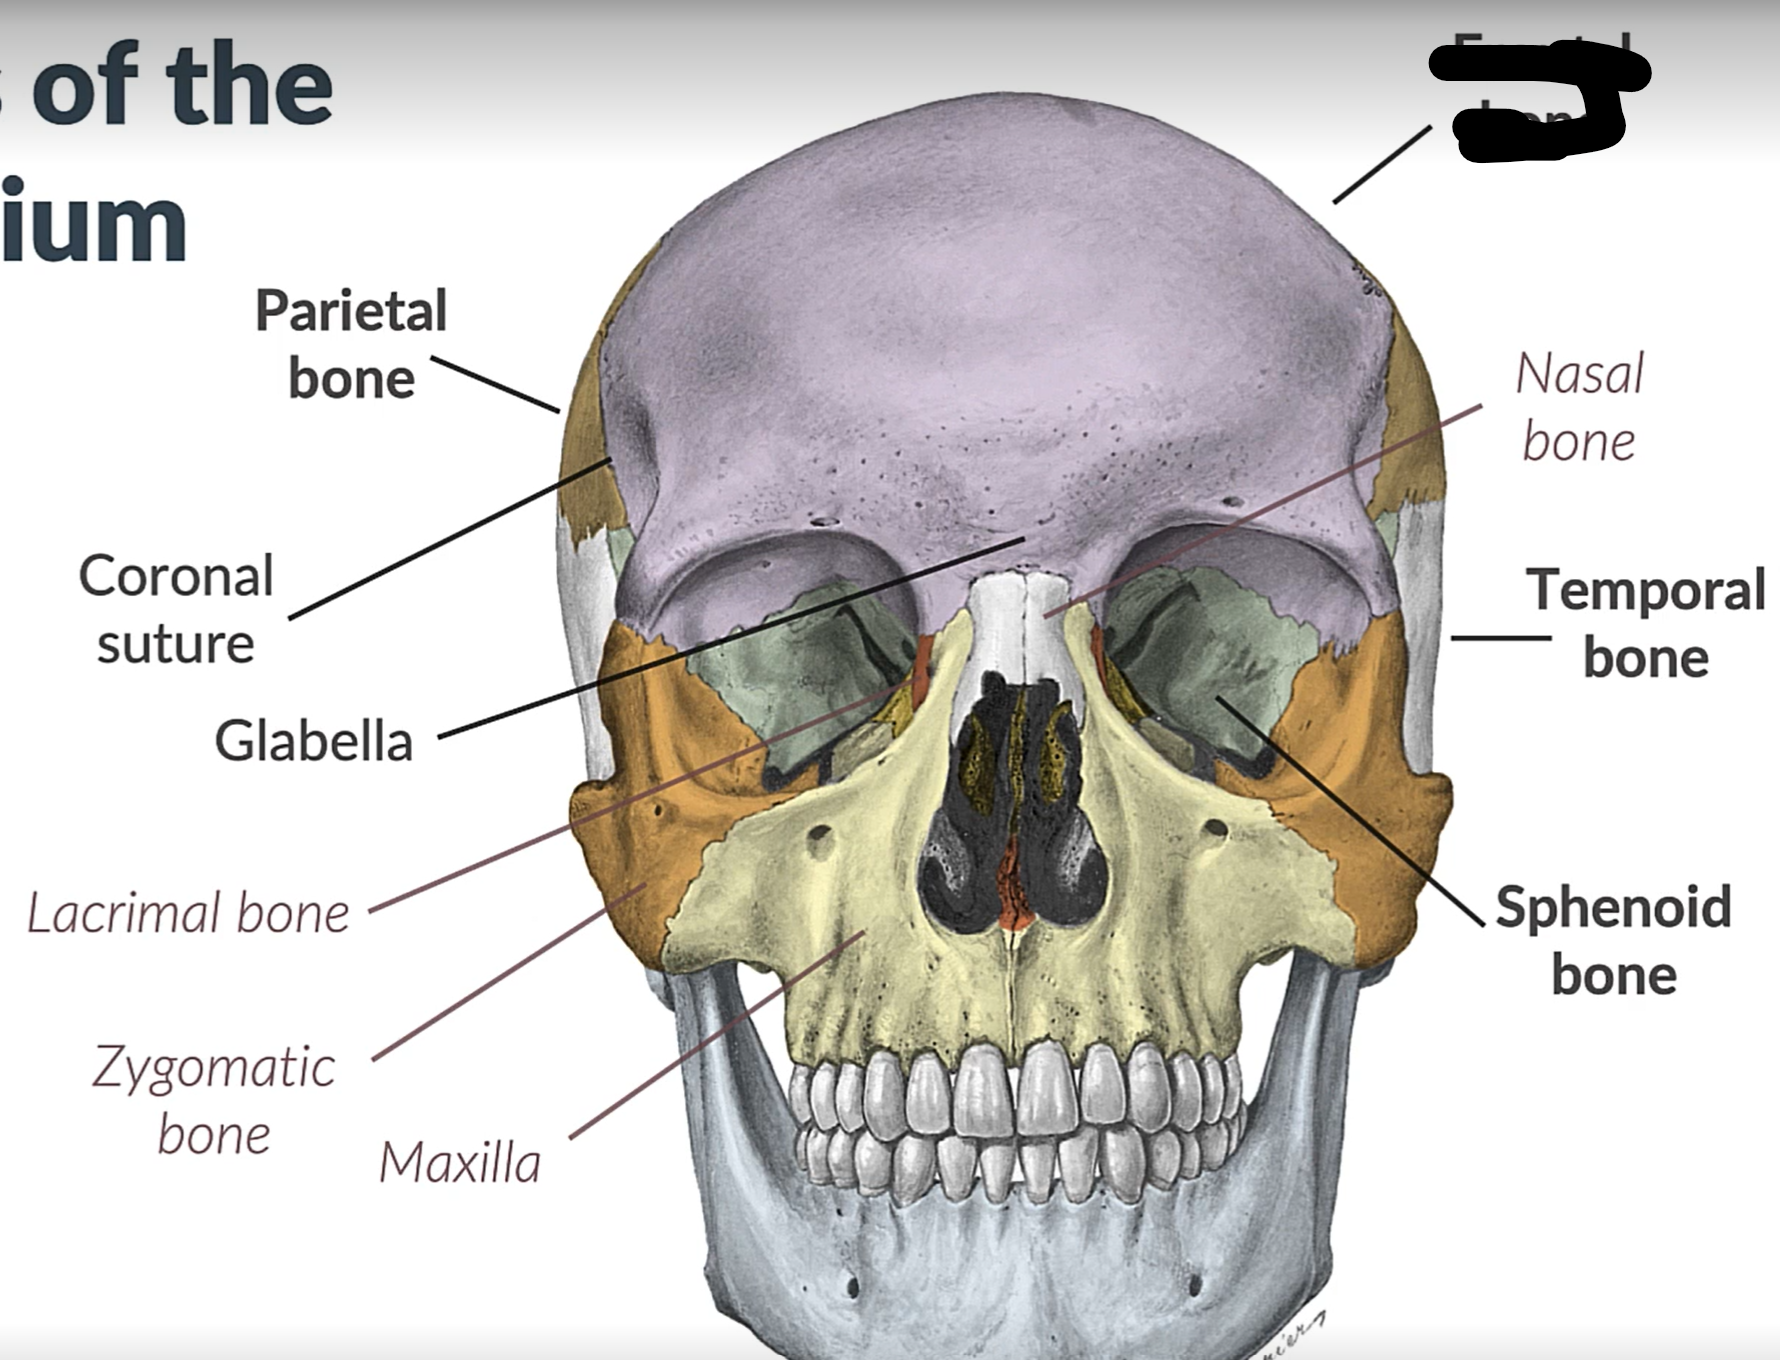

Parietal bone

Frontal bone

Temporal bone

Sphenoid bone

Zygomatic bone

Lacrimal bone

Coronal suture

Maxilla

Frontal bone

Coronal suture

Parietal lobe